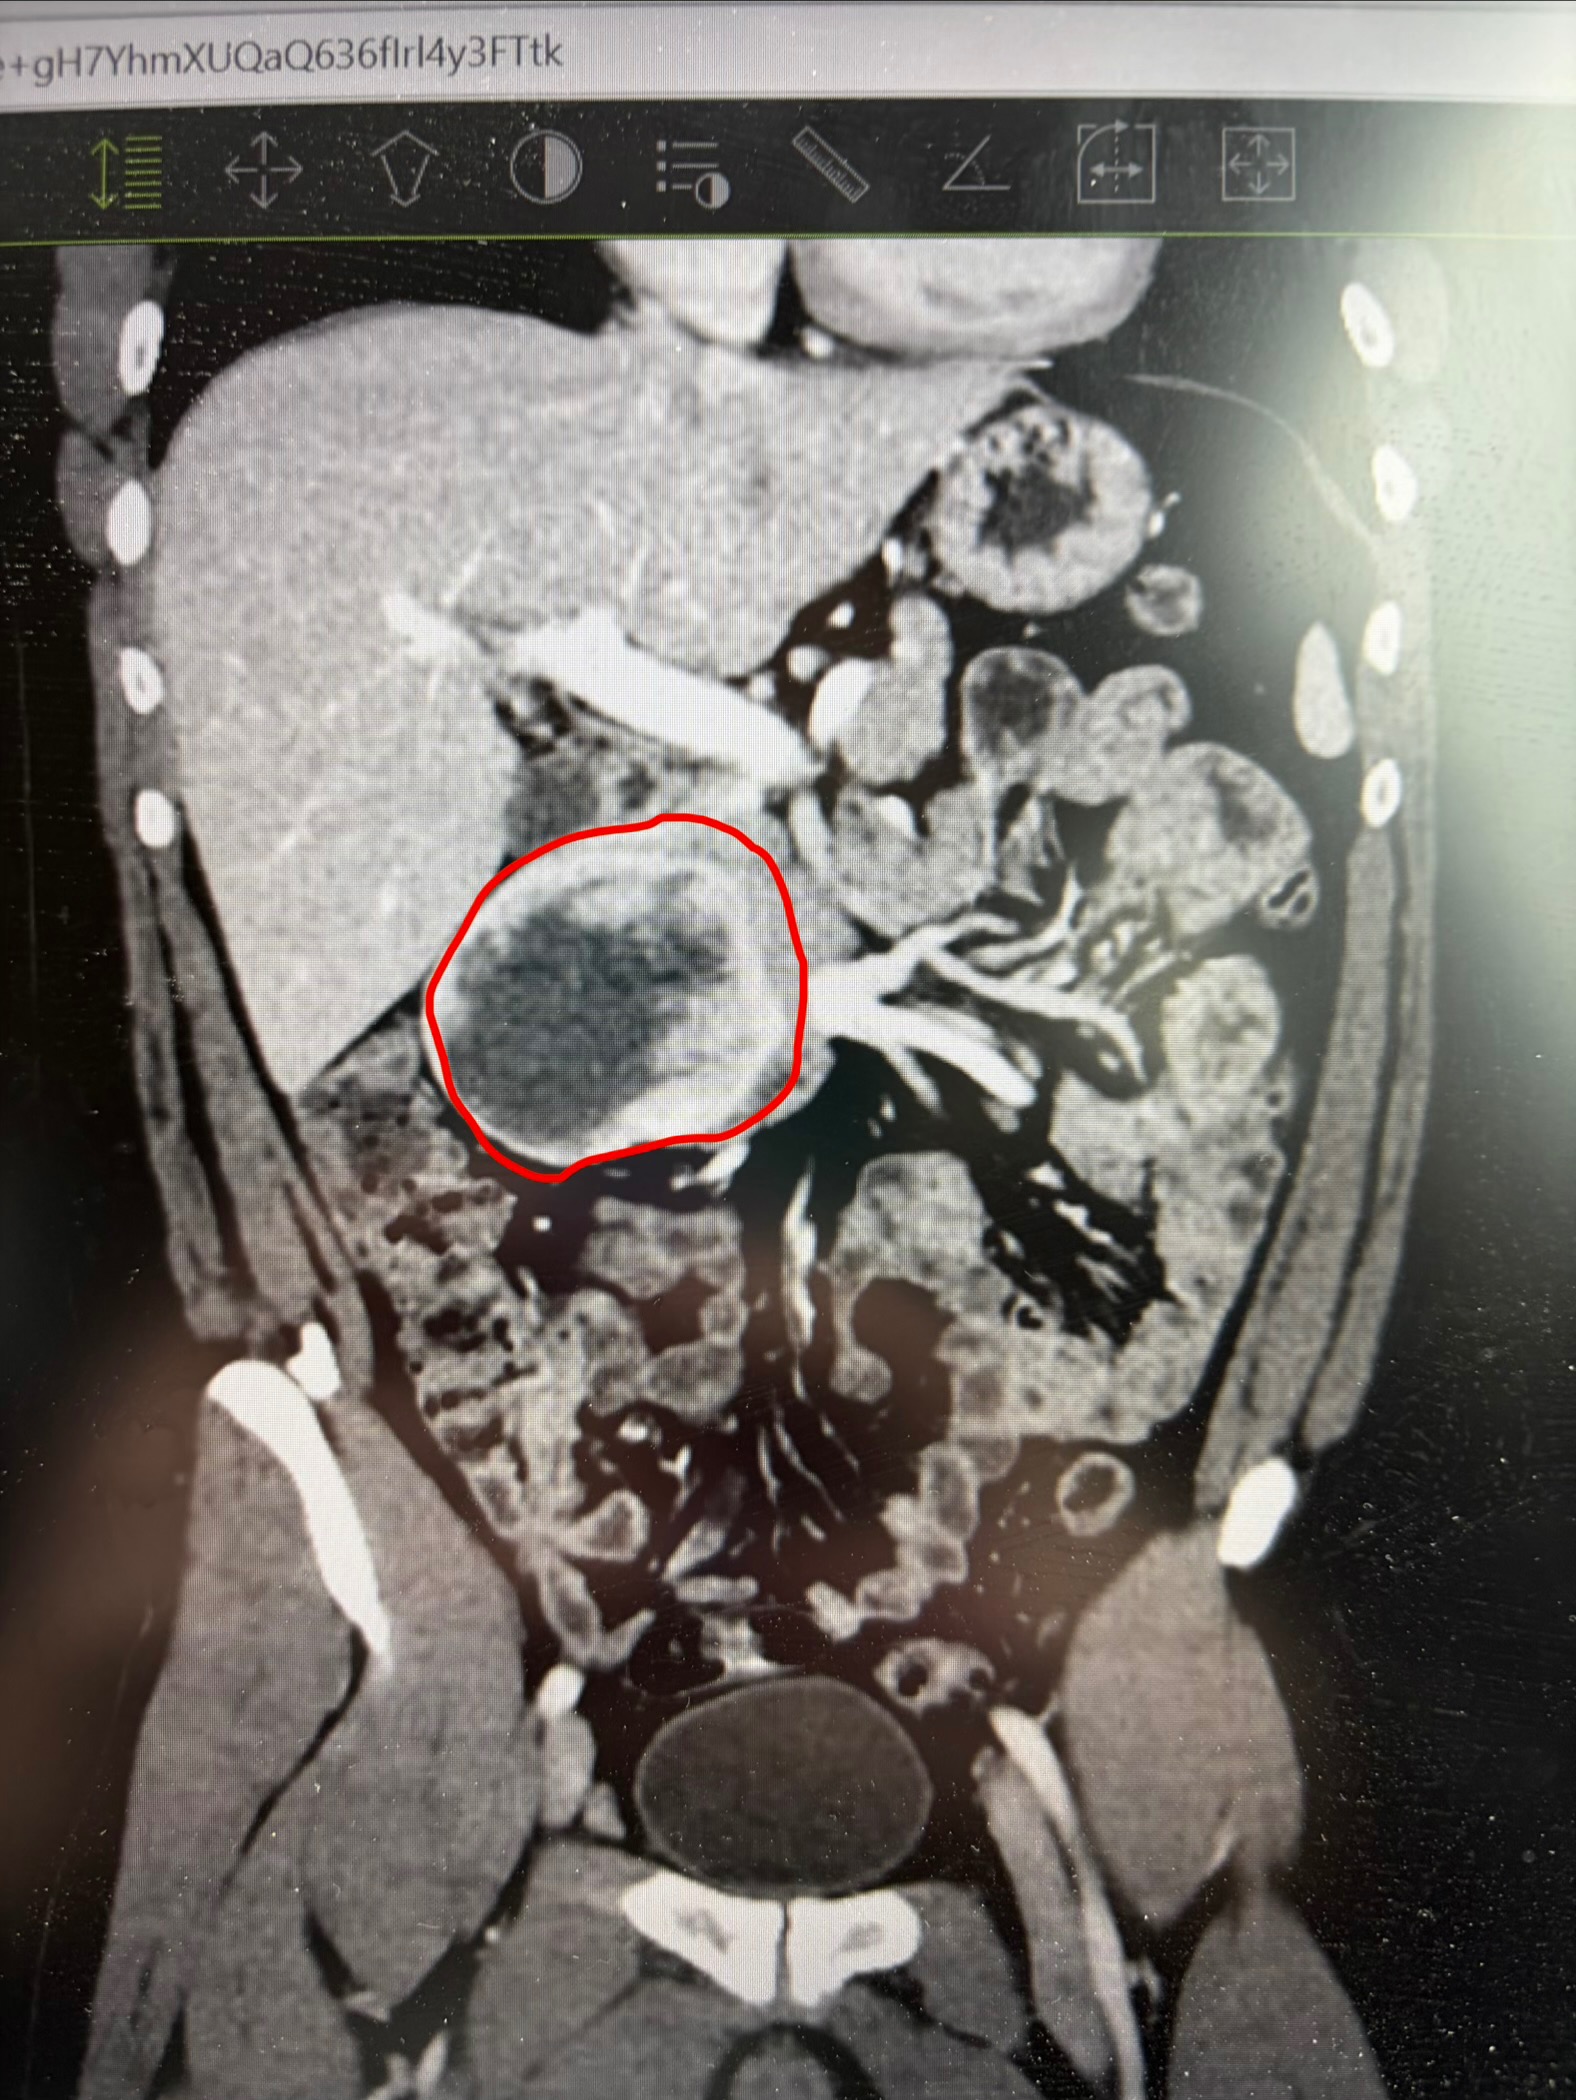

Kyle was having some horrible stomach pain among several other alarming symptoms, for several days, that landed him in the ER Tuesday night. After some bloodwork and a CT scan, he was admitted to the hospital for a large mass in his small intestines. Several possibilities were named as to what this could be, but until we got a biopsy with testing done, we did our best not to panic and stayed positive. Wednesday was a full day with no testing or answers, but Thursday was a busy day. After one failed Endoscopy in the AM, to obtain a biopsy for testing, we did have a successful biopsy, guided by Ultrasound that evening. But, of course, we have to wait for results.

Kyle has been diagnosed with GIST, or a Gastrointestinal Stromal Tumor. A very rare cancer typically found in adults aged 40-70. There is a genetic mutation that causes this cancer, however we don’t know what that is at this time. The doctor is hopeful for the success of removal of this mass, but until we hear from the GI Doctor and Surgeon, we won’t know a definite answer as to what our immediate future will look like. And furthermore, once the surgeon is able to perform the surgery, we won’t know for sure whether or not, it will require more mass removal if it did spread or not.